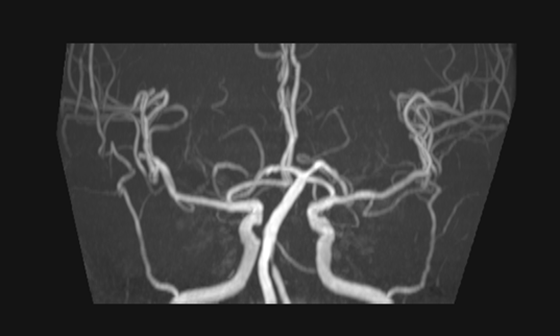

徐晶晶主治医师接诊患者后,立即向主任周文斌教授、张先龙副主任医师汇报。结合患者体征病史、影像资料等,凭借丰富的临床经验,周文斌教授高度怀疑患者为“脑干梗死”,很可能是罕见脑梗死。医生们对症下药,经过抗血小板聚集,调脂、稳定斑块,清除自由基,护脑等对症支持治疗后患者病情有所好转,呼吸有所平稳。

在进一步的头颅磁共振检查中,印证了周文斌教授最初的猜测,图像上赫然出现的“心形图案”,即脑梗死中罕见的双侧延髓内侧梗死。